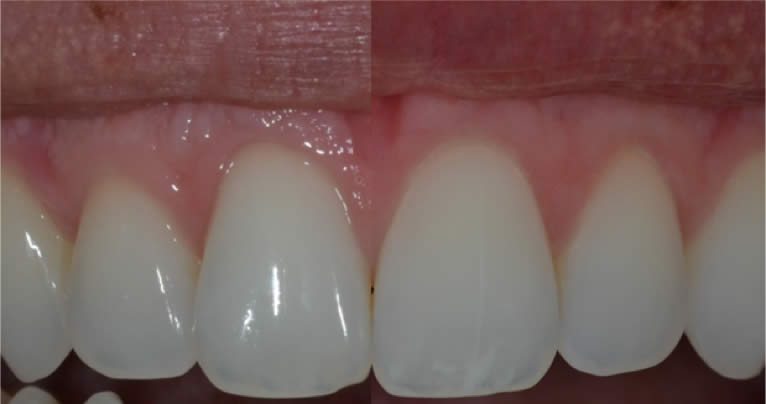

Elle permet d’envoyer énormément d’informations au prothésiste sur les états de surface, sur la répartition des masses, sur les caractérisations, sur les effets de translucidité.

A cela peut être ajouté un travail sur la lumière avec les flashs. L’idéal étant de les déporter pour améliorer la perception des états de surface. Un éclairage avec un angle de 45° apporte une lumière douce qui met en valeur les lignes de transition.

Il faudra faire attention au changement de teinte lié à la déshydratation : une dent déshydratée paraîtra plus claire. Il est donc conseillé de prendre la teinte en début de séance et d’attendre la réhydratation de la dent avant de valider le résultat esthétique final.

Le système de lumière polarisée Polar Eyes complète avantageusement les informations transmises au prothésiste. Cette technique va permettre de s’affranchir des reflets de l’émail et ainsi donner un maximum d’informations sur les répartitions des masses dentaires.